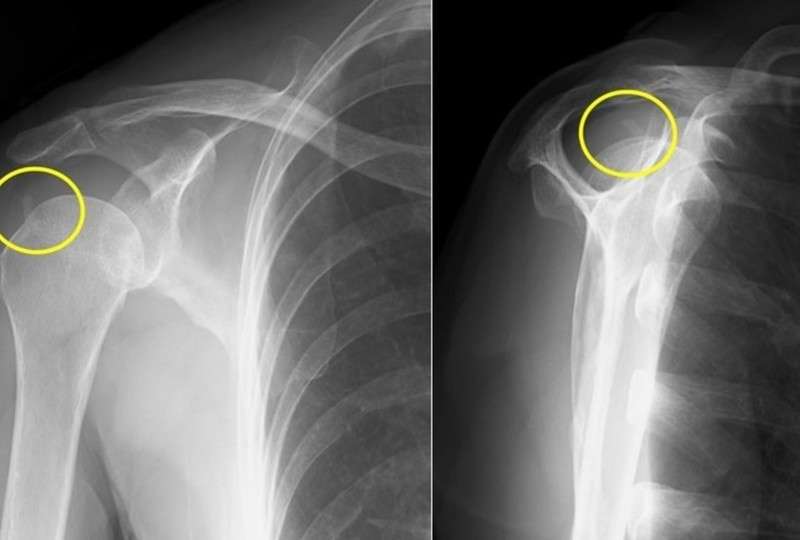

レントゲン検査

黄色い丸で囲んだ部分もみると石灰が見えます。